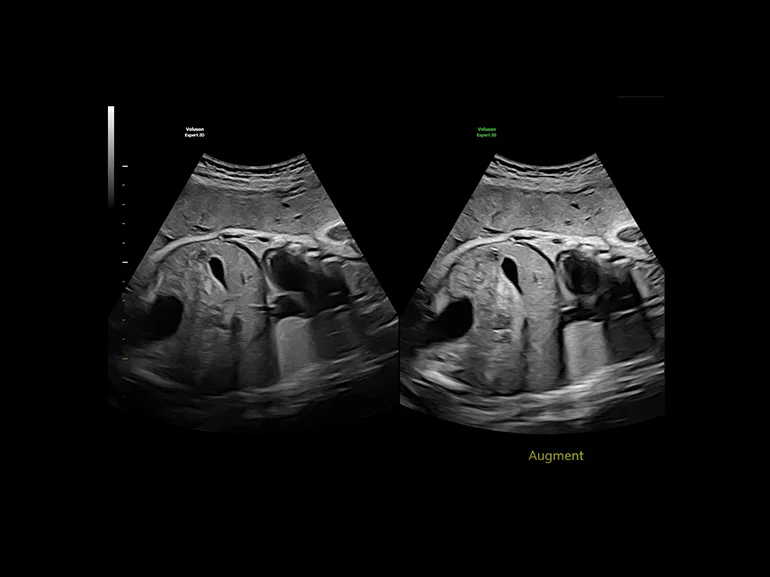

Повысьте степень проникновения для получения более достоверного результата и более четкого изображения даже в сложных условиях сканирования с помощью функции Augment.